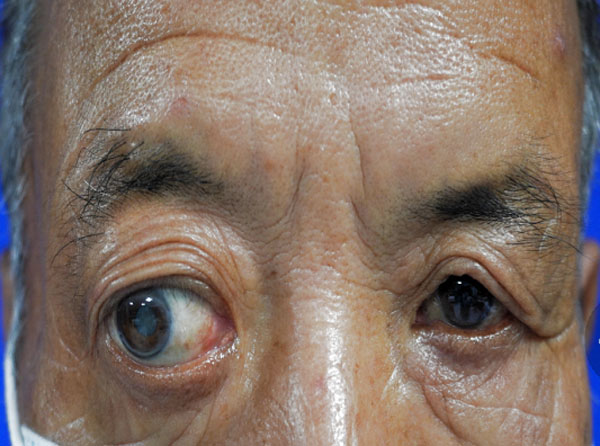

眼眶肿瘤,可能是会让患者失去光明的“定时炸弹”。

眼球突出是最常见的临床表现,当然少数患者是眼球本身的疾患引起眼球增大,如高度近视,我们称为假性眼球突出。眼突较轻时,仅外观不对称;程度较重时,眼球会移位、运动障碍、复视、视力下降,直至眼睑无法闭合,引起暴露性角膜炎。如果是恶性肿瘤造成的,还可能远处转移,危及生命。

眼球突出并不一定意味着肿瘤,如外伤性突眼,主要是头面部外伤引起眶骨骨折、眶内出血所致;内分泌性突眼与甲状腺功能亢进有关,还会伴有上睑退缩的特征性表现;炎症性突眼有急性的蜂窝组织炎和慢性炎症,常伴红、肿、热、痛等表现;血管性突眼的特点是低头、屏气时眼突会加重,因此呈间歇性。

当您因眼球突出而就诊时,医生会询问一些相关“线索”,如年龄、病变发展速度、有无外伤、有无疼痛甚至全身血液情况、甲状腺功能等等,都对正确的鉴别诊断极为重要。例如小儿眼球突出,特别是双侧者,就需排除白血病。